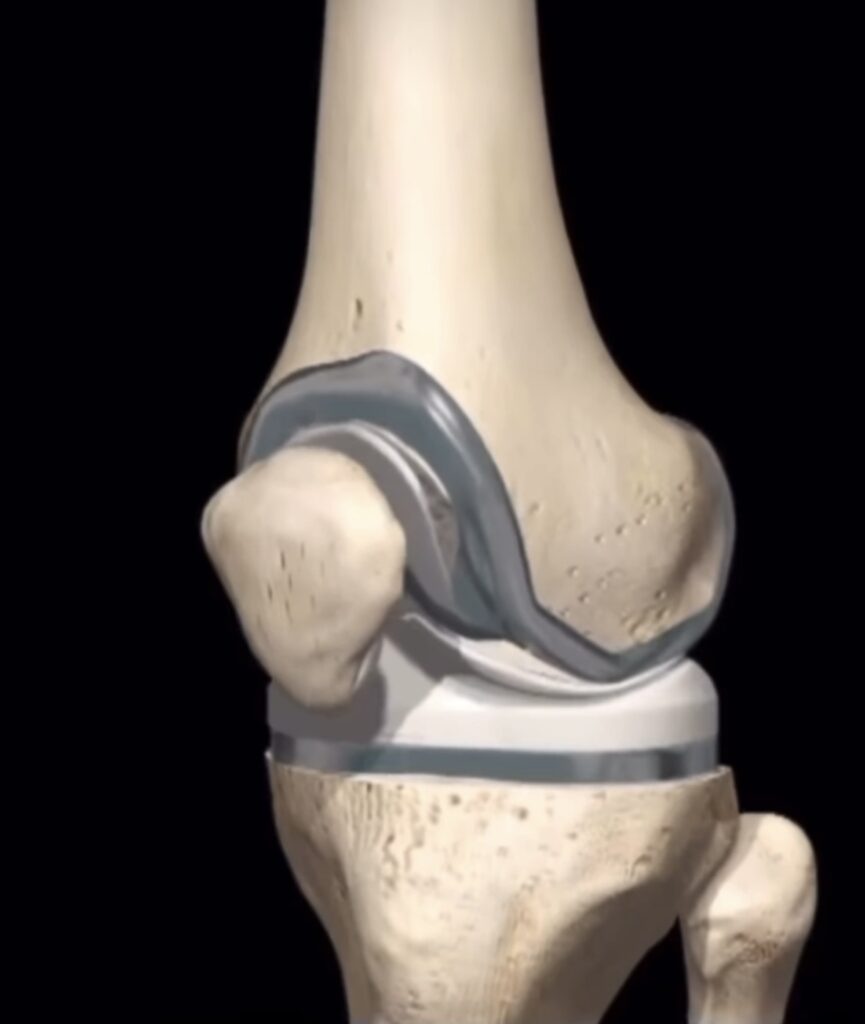

A artroplastia é a cirurgia onde se substitui a articulação acometida pela artrose grave por uma prótese, ou seja, uma “junta artificial”.

A artroplastia pode ser total, quando toda a articulação é substituída, ou parcial, quando parte dela recebe a prótese. No caso do joelho, a artroplastia parcial é chamada de unicompartimental, pois apenas um compartimento está degenerado e é substituído.

Existem diferentes tipos de próteses e cada uma delas tem suas indicações específicas baseadas no grau da doença, instabilidade, defeito ósseo, deformidade, rigidez articular, entre outras. É fundamental a avaliação por um especialista para o planejamento adequado!